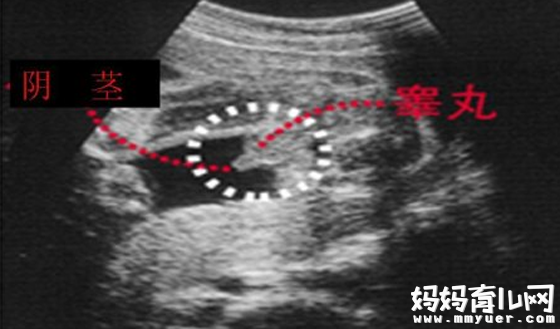

男宝宝B超图

"凸出的东西" 是他的标记: 你们看到圆圆的是DANDAN,如果看到圆圆的加小肠的就是全部JJ